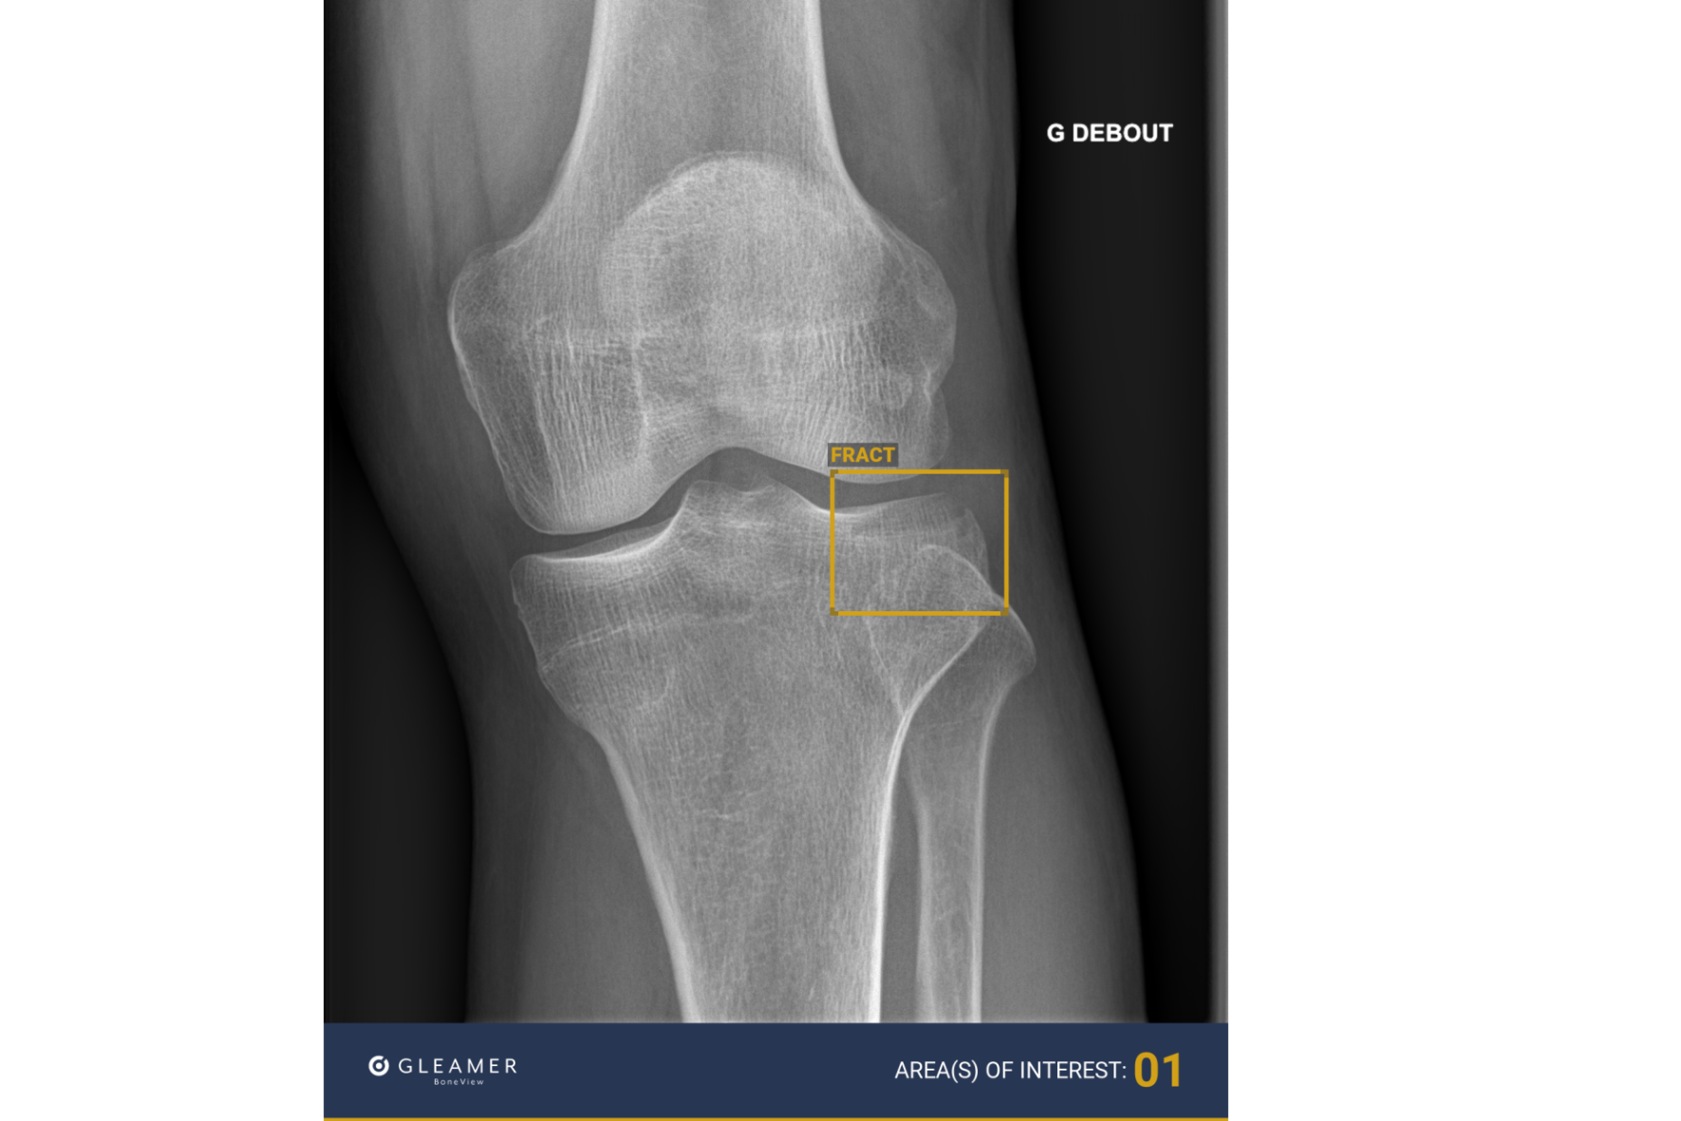

Prosjektleiarane fortel at programmet BoneView er eit avgjerdsstøtteverktøy som analyserer røntgenbilete av skjelettet under nakkenivå for pasientar over to år. Verktøyet er trent til å oppdage brot, væske i ledd og ledd som er ute av stilling.

– BoneView kan analysere bilete og identifisere brot på berre eitt til to minutt, forklarar Jørgensen.

– Systemet gir tre moglege svar; ingen funn, moglege funn med usikkerheit, eller sikre funn av brot. Dette gjer det mogleg for radiografar å raskt avgjere om pasienten kan sendast heim eller treng vidare behandling.